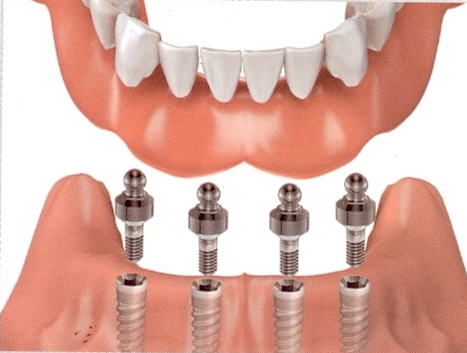

Современные съемные протезы на локаторах: Фото и примеры